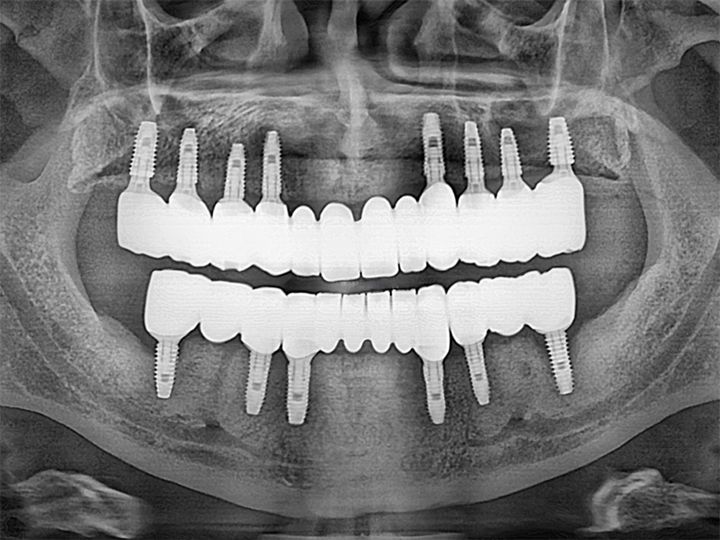

ハル歯科医院は、最先端のインプラント歯科治療に特化したクリニックです。代表のジョー・ハング院長は日本の神奈川歯科大学を卒業し、両国での歯科医師免許を保持。さらに、韓国で専門医資格を取得し、口腔外科など高度な手術経験も豊富です。すべての治療を院長自らが行う専任診療制を採用しており、流暢な日本語で対応可能。「デジタルインプラント」や「無削除ラミネート」などの最新のデジタル歯科治療を、日本の約半額で受けられます。仁川・金浦空港から乗り換えなしで行ける孔徳(コンドッ)駅すぐとアクセスも良好で、旅行者にも便利な立地となっています。

インプラント

匿名さん

日本でインプラント施術を行う予定でいましたが、色々と調べた結果、価格面でこちらで行うことを決めました。

先生との会話も日本語で行えて、海外で施術を受けるという当初の不安は無くなりました。

施術の内容や予算も相談して決められたので安心できました。また継続して訪問させていただこうと思います。

日本のインプラントは高額なのでネットで韓国の歯科医院を探してました 日本語対応の歯科医はいくつかありましたが せつ術医師に直接日本語で話せるということでハル歯科医院を選びました 先生はとても親切で最初の説明からわかりやすく こちらの質問にも全て親切に答えていただきました 5本のインプラントをいちどに入れていただいたのですが とてもスムーズに5本入れることができました 費用もkonest やホームページに書いてあるとおりで 1本140万wから120万wにディスカウントしてもらい レートも一円 10w で計算していただきました 3ヶ月後にまた来院します この歯科医院を選んで良かったと思ってます